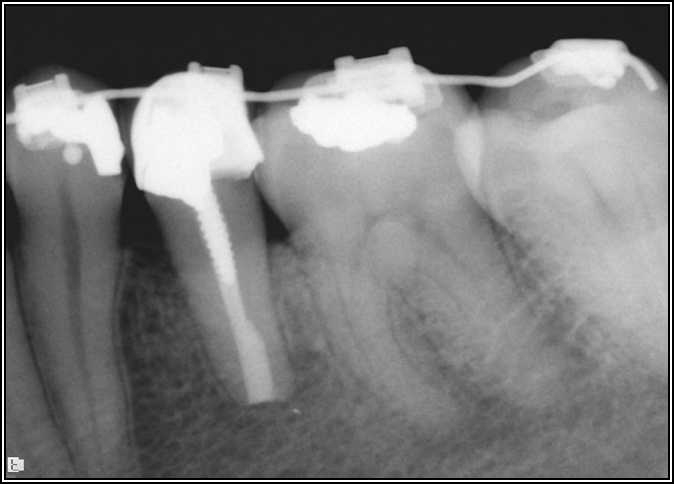

Occlusion is one of the most overlooked areas in endodontics; however, other than remaining structure, it is the most important factor.7 Patients who are heavy bruxers can cause the need for a root canal from the lateral forces. Patients who clench pose a different challenge with apical forces, yet the damage from both can be the same. Figure 7 shows a patient with bruxism. The patient had pain in response to hot and cold stimulus, and the clinicians needed a bitewing to determine which tooth was causing the pain. From the periapical (PA), it was clear that tooth No. 2 had a large problem, No. 3 had a crown, and No. 4 had a large restoration. Any of the three may have been the source of the problem.

With the bitewing shown in Figure 8, it became clear there was gross decay in tooth No. 3 that could not be seen on the PA, and there was a periodontal defect, a pulp stone, in No. 2. There was also a class V lesion revealing the bruxism, flat occlusion, multiple restorations in No. 30, a post in No. 31, and decay on No. 2 as well. The post in No. 31 was useless because when a post is placed, it must be the right length, width, and size. If the post is too short, there will be a greater fulcrum and the tooth will break. If it is too long, the clinician can break it by wedging it. If it is too short, it will not hurt the tooth, but it will not provide any valuable function. It is overall preferable to do posts in teeth having just single restorations rather than abutments for bridges because those teeth are already under greater force. If the technique is not performed correctly, iatrogenic issues may result.

Fig 7. Bruxism.

Figure 7

Fig 8. Bitewing revealed decay and other problems.

Figure 8